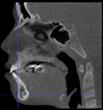

Three points determined the Acta plane: O, F right (FR), and F left (FL) (Table 2). Point O is the midpoint between the most craniodorsal point of the dorsum Sella and the most posterior dorsal point of the Basion in the midsagittal plane (Figure 1). Both points F are a result of the intersection between two lines: the line that connects the most inferior points of the lower orbital margins, right and left, and a line perpendicular to this line that runs through the most external points of the orbital margins, right and left (Figure 2). The new transverse reference plane, the Acta plane (Figure 2), is created by connecting the O-point (Figure 1) with FR and FL (Figure 2).

Figure 1.

Point O (green dot) is the midpoint between the dorsum Sella (Se) (red dot) and the Basion point (Ba) (yellow dot).